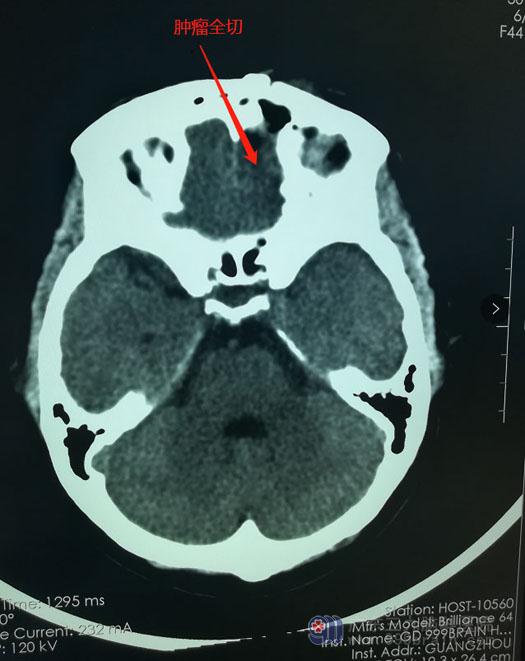

最终,陈阿姨决定听从医生的建议,接受手术治疗。由鲁明主任主刀在全麻下为陈阿姨实施经左侧眉弓锁孔入路行前颅窝底左侧额部镰旁脑膜瘤切除术,手术过程顺利,病变被完全切除。

采用经眉弓锁孔入路,脑组织及皮肤的损伤都非常小,手术切口只有眉毛的长度,采用美容缝合,如果不仔细观察,完全看不出来陈阿姨是做过脑部手术的人。术后,陈阿姨恢复良好,头痛头晕症状消失,没有出现视力、肌力等其他神经功能的损伤。